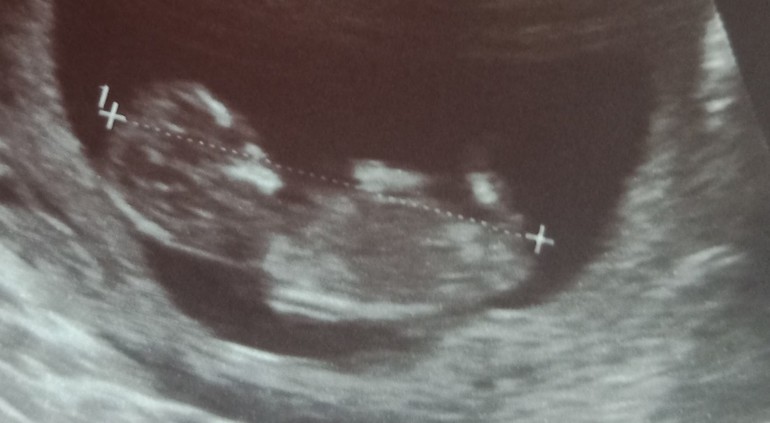

Ножка или половой бугорок?)

Как думаете, это бугорок или ножка?)

Мне видится мальчик по последнему фото. Над крестиком небольшой такой вверх, у девочек он больше параллелен линии спины что ли.

бугорок у обоих полов есть, а пол определяют по его положению - это должен врач на скрининге посмотреть и определить

Мальчик ,,,вот мой сыночек в 12 недель,,и половой бугорок его